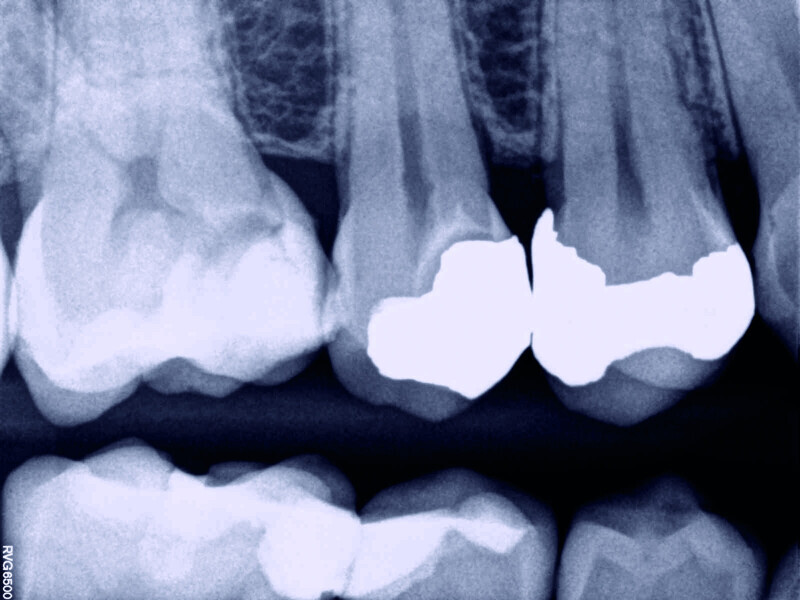

Direct pulp capping as a conservative procedure to maintain pulp vitality